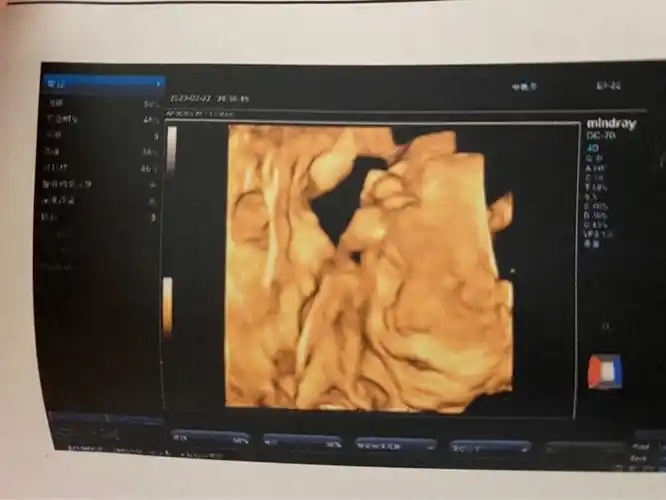

胎儿唇腭裂的超声诊断

超声诊断胎儿唇腭裂